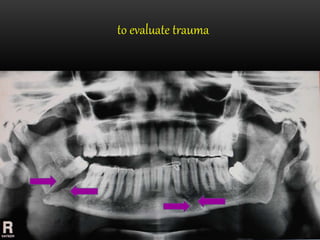

to evaluate trauma